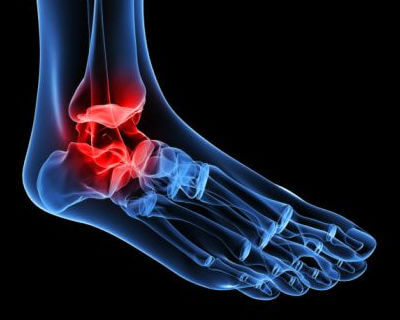

Hvordan ankel slidgigt forekommer

Denne form for gigt er forårsaget af progressiv slid på ankelledets brusk. Det er almindeligt, at vores ankler bliver stive og udvikler deformiteter, som vi ældes.

Klassiske bensporer kan også forekomme, hvilket gør det til en meget smertefuld, såvel som bevægelses begrænsende tilstand.